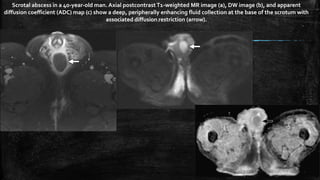

Scrotal abscess in a 40-year-old man. Axial postcontrastT1-weighted MR image (a), DW image (b), and apparent

diffusion coefficient (ADC) map (c) show a deep, peripherally enhancing fluid collection at the base of the scrotum with

associated diffusion restriction (arrow).

Scrotal abscess ina 40-year-old man. Axial postcontrastT1-weighted MR image (a), DW image (b), and apparent diffusion coefficient (ADC) map (c) show a deep, peripherally enhancing fluid collection at the base of the scrotum with associated diffusion restriction (arrow).